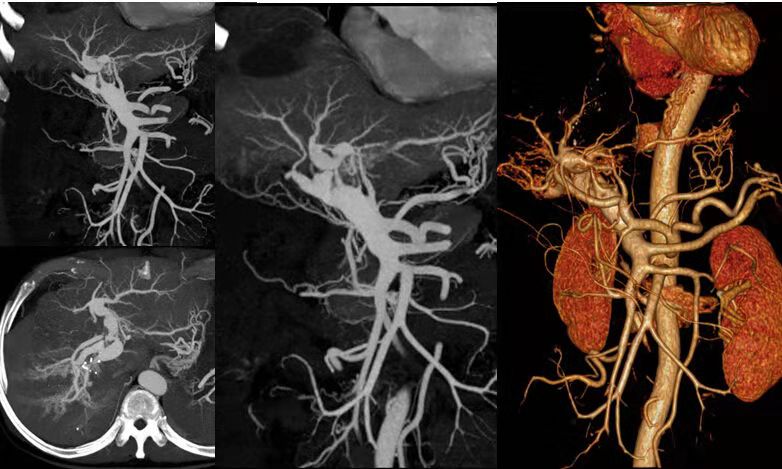

除開展全身(shēn)各部位常規檢查外,還先後開展了(le)全身(shēn)血管CTA成像、骨關(guān)節CT三維重建、磁共振擴散加權成像DWI、灌注成像PWI、磁敏感成像SWI、胰膽管水成像MRCP、泌尿系水成像MRU、内聽(tīng)道水成像、外周血管介入診療、消化(huà)道支架成形術、椎體(tǐ)成形術、椎間(jiān)盤消融術、經皮穿刺活檢術等新(xīn)技術。

腸系膜動脈CTA

全身(shēn)多部位血管造影及介入治療